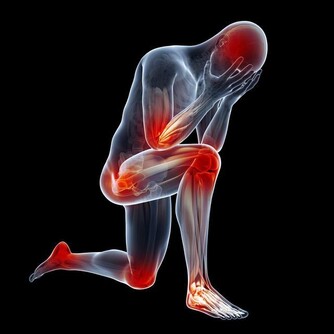

高血壓,是指以體循環動脈血壓(收縮壓和/或舒張壓)增高為主要特徵(收縮壓≥140毫米汞柱,舒張壓≥90毫米汞柱),可伴有心、腦、腎等器官的功能或器質性損害的臨床綜合徵。高血壓是最常見的慢性病,也是心腦血管病最主要的危險因素。

高血壓產生的原因有遺傳因素、精神和環境因素,生活習慣因素等,但是最常見的一個種原因是年齡原因。隨著年齡的不斷增長,40歲以上的中老年群體極易患高血壓,主要原因是人體血管內的各種代謝雜物擁堵與血管中,造成血液流量不穩,出現高血壓現象。作為一種常見的慢性疾病,高血壓可誘發冠心病、中風等多種致命的心腦血管疾病疾病,也被認為是中老年健康的“頭號殺手”,並且患上高血壓很難治愈,像不定時炸彈一樣伴隨終身。